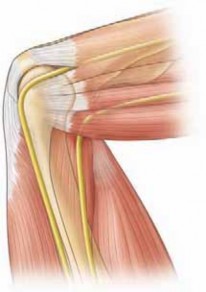

- Identify and protect the ulnar nerve, particularly if the fracture extends medially or if plate fixation is planned. Routine transposition is not required unless the nerve is involved in the fracture site or hardware placement threatens it.